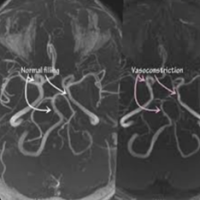

Síndrome de Vasoconstrição Cerebral Reversível

O que é a síndrome de vasoconstrição cerebral reversível (SVCR)? A síndrome de vasoconstrição...